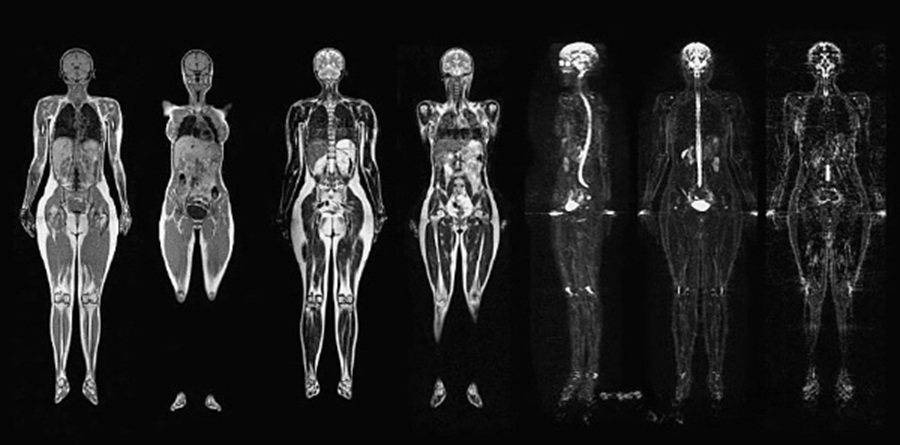

МРТ всего тела позволяет визуализировать широкий спектр анатомических структур и выявить различные патологические изменения. В ходе обследования получают изображения головного мозга, шеи, позвоночника, грудной и брюшной полостей, малого таза, крупных суставов и мягких тканей конечностей. Это обеспечивает возможность одновременной оценки состояния центральной нервной системы, внутренних органов, опорно-двигательного аппарата и сосудистой системы.